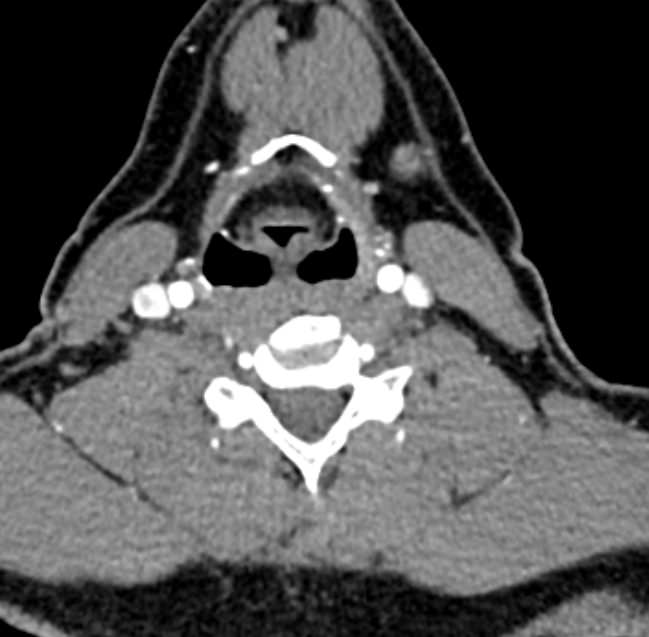

Мультиспиральная КТ сосудов шеи (КТ-ангиография) включает в себя сканирование брахиоцефальных артерий, то есть как сосудов кровоснабжающих головной мозг, так и проксимальные отделы плечевых артерий. Это крупные сосуды, которые отходят от дуги аорты и, разветвляясь, уходят в полость черепа. К ним относятся: брахиоцефальный ствол, общие, наружные и внутренние сонные артерии, подключичные и позвоночные артерии.

КТ сосудов шеи является высокоинформативным методом диагностики патологии брахиоцефальных артерий, который позволяет выявлять участки сужения, патологической извитости, определять развитие атеросклеротических бляшек ещё до того, как появились симптомы заболевания.

В наших медицинских центрах диагностика патологии магистральных сосудов шеи проводится на современных мультиспиральных компьютерных томографах экспертного уровня TOSHIBA AQUILION. Компьютерная томография относится к лучевым методам исследования, то есть для получения изображения внутренних органов используется рентгеновское излучение. Трубка томографа при помощи рентгеновских лучей послойно сканирует область исследования с минимальной толщиной среза от 0,5 мм, затем полученные данные трансформируются в объемные изображения. Оснащение аппаратов позволяет получать снимки и трехмерные реконструкции сосудистой системы превосходного качества, при этом пациент получает минимальную дозу облучения.

Для улучшения визуализации сосудистой системы обязательным является проведение контрастного усиления. Для этого пациенту внутривенно вводится йодсодержащий контрастный препарат, который активно поглощает рентгеновские лучи и обеспечивает яркую видимость даже мелких сосудов на фоне окружающих тканей.